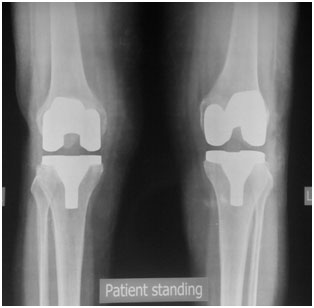

The x-ray appearance of a bilateral total knee replacement. Note that the plastic spacer between the bones does not show up in an x-ray.